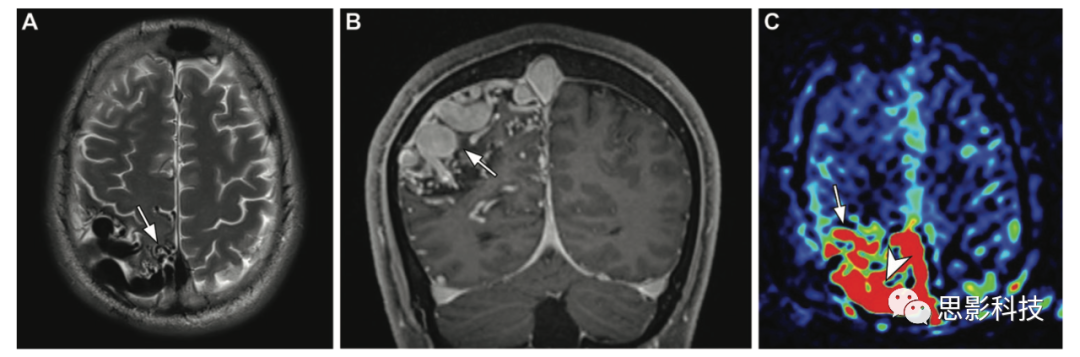

腦部典型軟腦膜型動(dòng)靜脈畸形,患者為34歲女性,癲癇發(fā)作。(A,B)軸位T2加權(quán)像和冠狀位高空間分辨率增強(qiáng)T1加權(quán)像顯示多個(gè)血流空隙,血管病灶的特征是右側(cè)頂葉內(nèi)嵌有一團(tuán)強(qiáng)化的管狀結(jié)構(gòu)(箭頭)。(C)ASL MRI表現(xiàn)為靜脈ASL信號(hào)偽影,表現(xiàn)為由于動(dòng)靜脈分流或快速傳輸,病灶(箭頭)和引流靜脈(箭頭)信號(hào)增強(qiáng)。